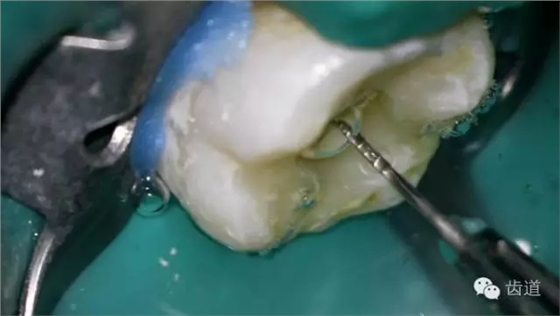

9. 預(yù)彎初尖銼探入根管

10. X線根尖片示尖 (近中及峽部)

11. 探入近中跟及峽部